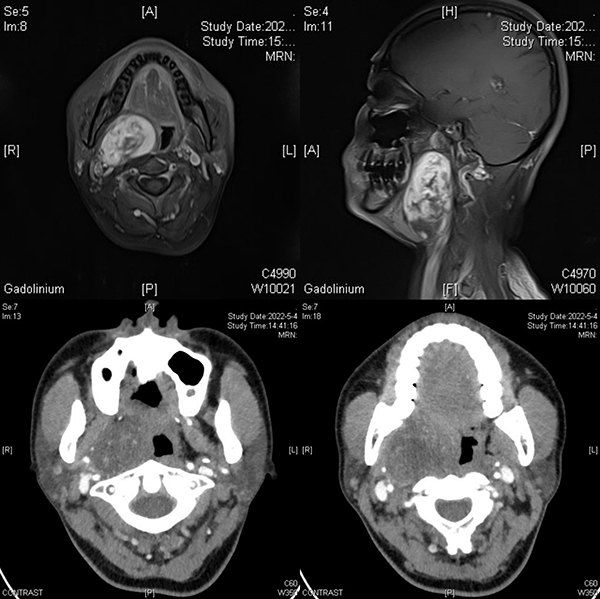

患者女性,47歲,因發(fā)現(xiàn)右頜下區(qū)腫物6年入住徐醫(yī)附院口腔頜面外科。入院后經(jīng)過(guò)頜面部增強(qiáng)CT和增強(qiáng)MRI檢查發(fā)現(xiàn)患者為右側(cè)口咽部腫物,腫物體積較大,上達(dá)顱底翼外肌水平,下至甲狀軟骨水平,致使半側(cè)咽腔堵塞。李家鋒主任憑借影像學(xué)資料及多年的臨床經(jīng)驗(yàn),初步考慮為神經(jīng)鞘瘤可能。但由于腫物體積較大,位于咽側(cè)深區(qū),毗鄰頸部重要大血管,致使該手術(shù)具有較大的難度和風(fēng)險(xiǎn)。既往對(duì)于該類型腫瘤,由于腫物體積較大,為避免重要血管及神經(jīng)損傷,術(shù)中需暫時(shí)劈開(kāi)下頜骨暴露腫物實(shí)施手術(shù)。術(shù)前和患者及其家屬溝通后,患者對(duì)下頜骨暫時(shí)劈開(kāi)心理負(fù)擔(dān)很大,希望盡可能避免下頜骨的劈開(kāi)。

為減少手術(shù)創(chuàng)傷及考慮到患者及其家屬?gòu)?qiáng)烈要求,避免下頜骨暫時(shí)劈開(kāi),李家鋒主任、呂中靜博士在術(shù)前經(jīng)過(guò)周密考慮并制定詳盡的手術(shù)計(jì)劃,帶領(lǐng)團(tuán)隊(duì)成員通過(guò)頸外入路囊內(nèi)摘除方式成功摘除腫瘤。術(shù)中發(fā)現(xiàn)該患者為來(lái)源于迷走神經(jīng)的神經(jīng)鞘瘤,李家鋒主任、呂中靜博士及團(tuán)隊(duì)成員在手術(shù)實(shí)施過(guò)程中,精準(zhǔn)分離,充分保護(hù)頸內(nèi)外動(dòng)靜脈及迷走神經(jīng),該患者術(shù)后并無(wú)相應(yīng)的神經(jīng)癥狀手術(shù)并發(fā)癥的出現(xiàn)。該患者在術(shù)后1周順利出院。該手術(shù)的成功實(shí)施,不僅最大程度減輕了患者的身體傷害,降低了患者經(jīng)濟(jì)負(fù)擔(dān),還加速了患者術(shù)后康復(fù),縮短了術(shù)后康復(fù)時(shí)間。